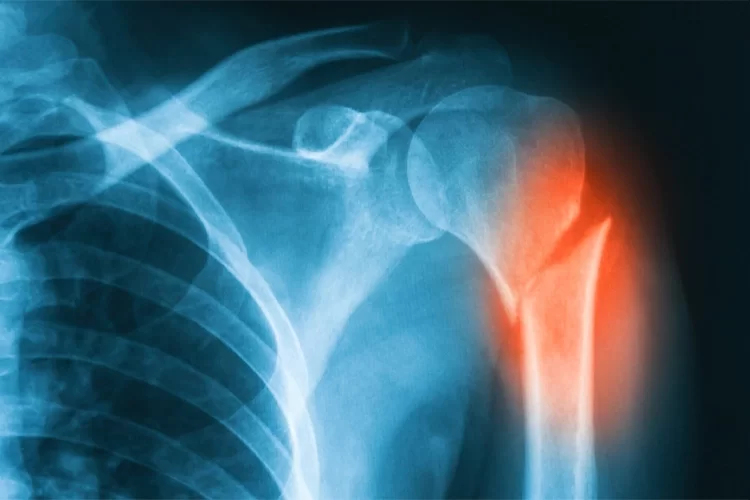

تصویر نمای رادیولوژی شکستگی پروگزیمال هومروس در یک بیمار سالمند

شکستگی پروگزیمال هومروس (Proximal Humerus Fracture) یکی از شایع ترین شکستگی های استخوان بازو به ویژه در افراد مسن است. این نوع شکستگی عمدتاً در اثر زمین خوردن روی دست باز یا تصادفات ایجاد می شود و بسته به میزان جابجایی قطعات، روش های درمان متفاوتی دارد. در این مقاله به بررسی کامل این شکستگی و راهکارهای درمانی می پردازیم.